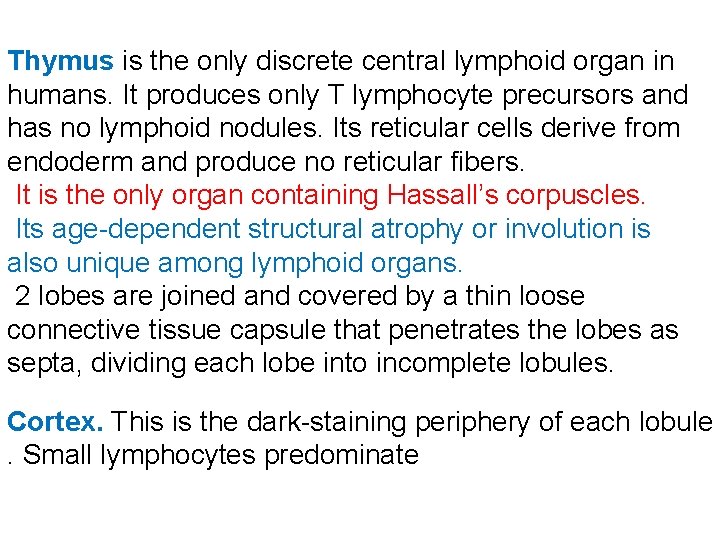

Thymus is the only discrete central lymphoid organ in humans. It produces only T lymphocyte precursors and has no lymphoid nodules. Its reticular cells derive from endoderm and produce no reticular fibers. It is the only organ containing Hassall’s corpuscles. Its age-dependent structural atrophy or involution is also unique among lymphoid organs. 2 lobes are joined and covered by a thin loose connective tissue capsule that penetrates the lobes as septa, dividing each lobe into incomplete lobules. Cortex. This is the dark-staining periphery of each lobule. Small lymphocytes predominate